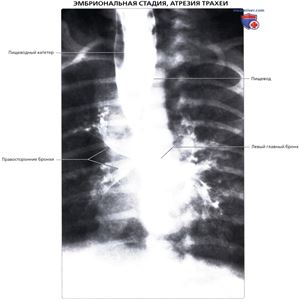

Рентгенограмма при атрезии трахеи у новорожденного

Посмертная рентгенография младенца с атрезией трахеи, ПЗ проекция: определяется введение контрастного вещества через катетер в просвете органа, затеняющего пищевод и аномальные правый и левый бронхи, начинающиеся от боковых стенок пищевода. Считается, что атрезия трахеи обусловлена аномально вентральным положением примитивных трахеопищеводных складок с перекрыванием просвета развивающейся трахеи. Поскольку бронхи образуются из передней кишки, они сохраняют примитивное сообщение с пищеводом.